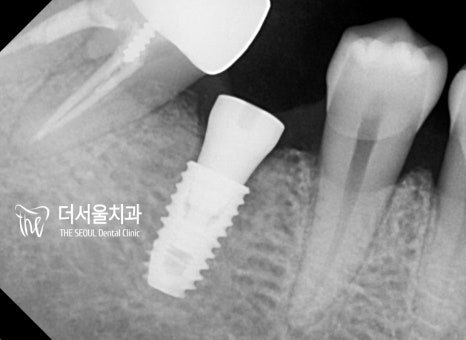

이렇게 정확히 계산된 계획을 토대로

본격적인 식립 과정에 들어갔습니다.

회복 기간을 줄여드리기 위해

최소절개를 이용하여 도와드렸죠.

이후 옆에 있는 인접치들과의 위치 관계를 따져

올바른 교합과 컨택을 조정 할 예정입니다.